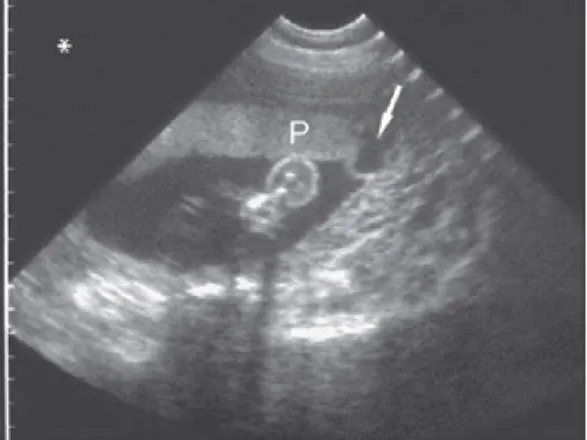

③ 초음파는 태반 박리의 증거를 보여줄 수 있다. (Fig 256-1)

: 다만 민감도는 25%이고 특이도는 90%

B. 태반 박리. 18주 산모, 시상단면에서 태반 뒤쪽의 혈종 (H). 태반은 (P) 뒤쪽 벽에 위치한다.